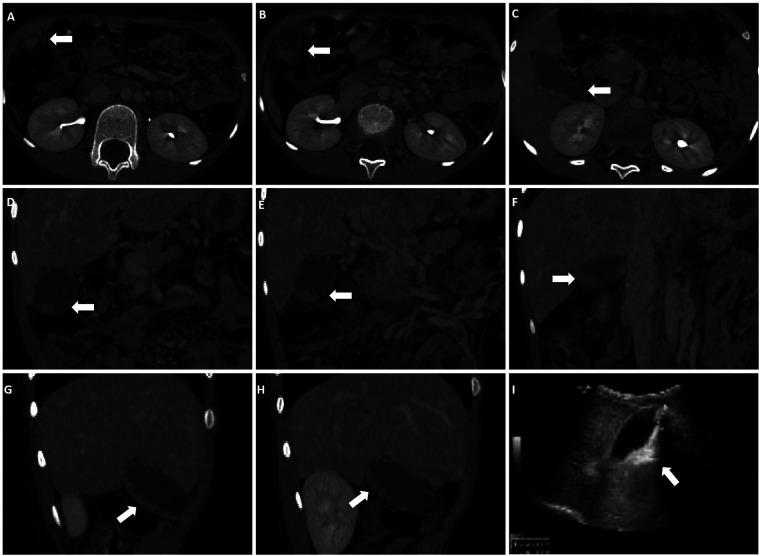

PL was diagnosed in 18.4% of patients treated with CTX, primarily through ultrasound, which revealed hyperechoic material within the gallbladder. Compared with the non-PL group, patients with PL were older and taller, with no significant differences in CTX dosage ( = 0.915). Patients with PL also had higher rates of digestive and neurological infections (both  < 0.001). Serum analysis revealed distinct liver and kidney function markers in the PL group, including lower levels of total bile acids, adenosine deaminase, and lactate dehydrogenase, and higher creatinine levels (all  < 0.05). Discontinuation of CTX led to symptom resolution in most cases, and all cases of PL resolved within three months.

The occurrence of PL is not significantly related to CTX dosage. Furthermore, the rate of CTX metabolism and excretion may play a key role in PL development. Overall, the findings demonstrate that ultrasound is an effective tool for monitoring the development of PL in children receiving CTX and that discontinuation of CTX could be an effective treatment for PL.

接受CTX治疗的患者中,18.4%被诊断为PL,主要通过超声诊断,超声显示胆囊内有高回声物质。与非PL组相比,PL组患者年龄更大、身高更高,CTX剂量无显著差异(P = 0.915)。PL组患者消化系统和神经系统感染率也更高(均P < 0.001)。血清分析显示PL组肝肾功能指标不同,包括总胆汁酸、腺苷脱氨酶和乳酸脱氢酶水平较低,肌酐水平较高(均P < 0.05)。在大多数情况下,停用CTX可使症状缓解,所有PL病例在三个月内均得到缓解。

PL的发生与CTX剂量无显著相关性。此外,CTX的代谢和排泄速率可能在PL的发生中起关键作用。总体而言,研究结果表明超声是监测接受CTX治疗儿童PL发展的有效工具,停用CTX可能是治疗PL的有效方法。